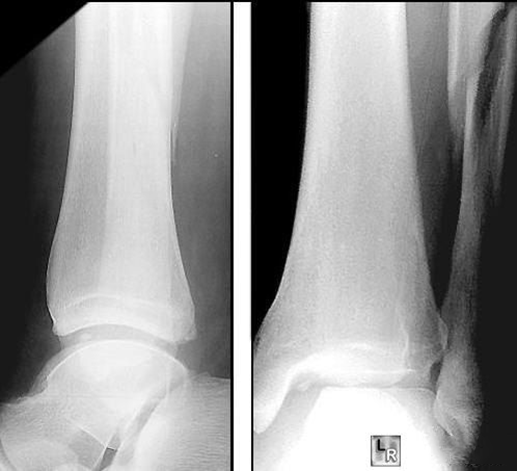

(4)Dupuytren 骨折

Dupuytren 骨折由法国外科医生 Dupuytren 于 1819 年首次描述。随后的几十年内,学术界对于'Dupuytren 骨折'与'Pott 骨折'是否存在区别,争论不断。根据腓骨骨折的不同位置,Dupuytren 骨折可分为低位 Dupuytren 骨折和高位 Dupuytren 骨折。按照踝关节骨折 Lauge-Hansen 分型,Dupuytren 骨折属于旋前外旋型或旋前外展型损伤。